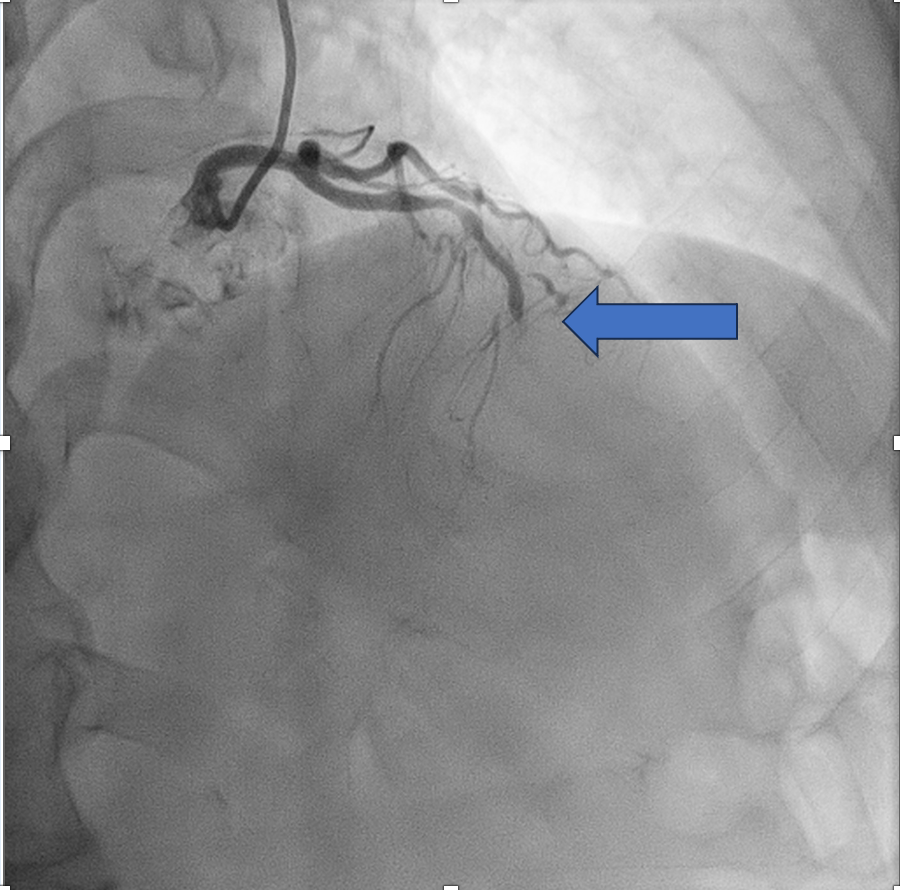

CORONARY ANGIOGRAM REVEALED CHRONIC TOTAL OCCLUSION AT THE MID LEFT ANTERIOR DESCENDING ARTERY (MLAD) WITH COLLATERALS FROM RIGHT CORONARY ARTERY. OTHER CORONARIES ARE NORMAL.

WE DECIDED TO INTERVENE THE CTO MLAD IN VIEW PERSISTENT ANGINA. BILATERAL RADIAL ARTERY PUNCTURE, WITH ANTEGRADE APPROACH. WE ENGAGED RIGHT CORONARY ARTERY WITH JR4 6 FR AND WIRED DOWN WITH RUNTHROUGH FLOPPY. ENGAGED THE LEFT CORONARY ARTERY WITH EBU 3.5 7FR. INITIALLY TRIED TO WIRE THE LAD WITH FINECROSS MICROCATHER (MC) USING SION BLACK WIRE BUT FAILED. SUBSEQUENTLY CHANGED TO GAIA 1ST AND MANAGED TO CROSS SUCCESSFULLY. IVUS SHOWED 360 DEGREE CALCIFICATION WITH 270 DEGREE CALCIFICATION MORE THAN 5 MM, IVUS CALCIUM SCORE 2. CALCIUM DEBULKING WAS DONE USING ROTABLATION WITH 1.5 BURR RUN 3 TIMES AT 220 KRPM FOR 10 SECS AND POLISHING RUN TWICE AT 140 KRPM. POST ROTA SHOWED PRESENCE OF FRACTURED CALCIUM WITH REVEBERATION SIGN. LESIONS WAS PREPARED FURTHER USING WOLVERINE 3.0 X 10MM AND 3.5 X 10MM. POST CUTTING BALLOON SHOT SHOWED NO DISSECTION, TIMI 3 FLOW AND RESIDUAL STENOSIS 30%. DECIDED FOR DCB WITH PANTERA LUX 3.0 X 20MM AND AGENT 3.50 X 30MM. FINAL SHOT SHOWED TIMI3 FLOW, NO DISSECTION SEEN. PATIENT REMAIN ASYMPTOMATIC AT 6 MONTHS AND REPEATED COROS SHOWED MODERATE STENOSIS AT MLAD WITH NEGATIVE FFR (0.92).